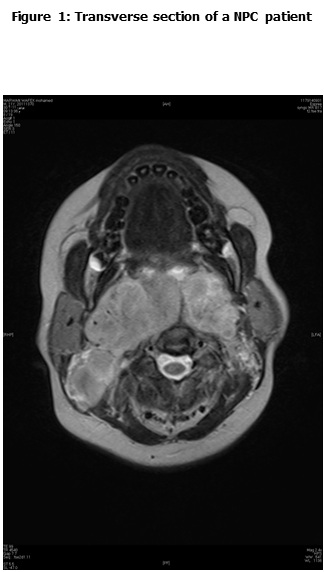

This is a retrospective study including all the newly diagnosed pediatric NPC who were diagnosed and treated at the Children Cancer Hospital Egypt (CCHE) during the period from July 2007 to December 2012. All imaging studies (e.g., CT or MRI scans) were reviewed by a senior head and neck radiologist for proper staging and assessment of tumor response. Patients were staged according to AJCC staging system. Modified version of the Response Evaluation Criteria in Solid Tumor (RECIST) was used to assess response.

This is a retrospective study including all newly diagnosed pediatric NPC at Children Cancer Hospital Egypt CCHE during the time period from July 2007 to December 2012. The patients' profiles were systematically reviewed for characteristics including pathology, laboratory, radiological work up and documented toxicities. All imaging studies (e.g., CT and MRI scans) were reviewed by a senior head and neck radiologist for proper staging and assessment of tumor response.

Pretreatment evaluation included a complete history and physical examination, complete blood count, serum biochemistry tests (including evaluation of electrolyte levels, hepatic and renal function tests), CT or MRI scans of the head and neck region, chest and bone scan. During therapy weekly examinations and laboratory evaluations were performed. Tumor response was assessed by clinical examination with appropriate MRI imaging studies after completion of neoadjuvant chemotherapy and at the end of radiotherapy.